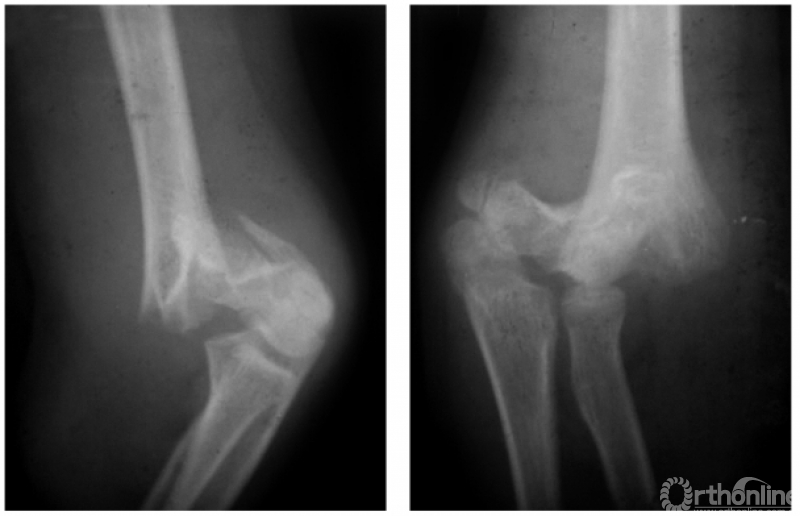

(三) 纵轴旋转型

例:髁上骨折,远折端有纵轴旋转致远近两断面的宽度很不协调(图6)。

图6

二、陈旧性肱骨髁上骨折

例1:陈旧性伸展型肱骨髁上骨折,致肘内翻畸形及前倾角消失(图7)。

图7